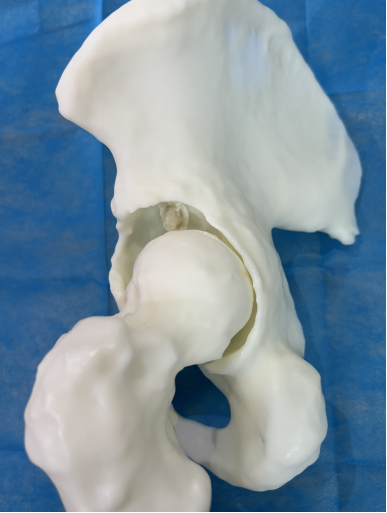

经过前期的治疗,现在左侧髋关节疼痛是影响李大妈生活质量的最大问题。通过对本次入院后髋关节CT的再次评估,张海军主任发现患者左侧髋臼骨缺损比3月前明显增多,普通假体无法完成手术,决定采用3D打印新技术评估髋臼缺损、模拟手术方案,经过3D打印模型和计算机测量评估,决定使用钽金属垫块和多孔钽杯重建髋臼。

依赖于术前准备充分,本例复杂髋关节翻修术不到2小时顺利结束。手术的顺利给了李大妈极大的信心,对她来讲,最大的心愿就是能尽快下地行走,我们团队为她量身定制个体化康复方案,经过几天的康复训练,李大妈生活基本自理,可以扶拐恢复行走,相信肌肉力量恢复后,李大妈回归正常生活的愿望很快就能实现!